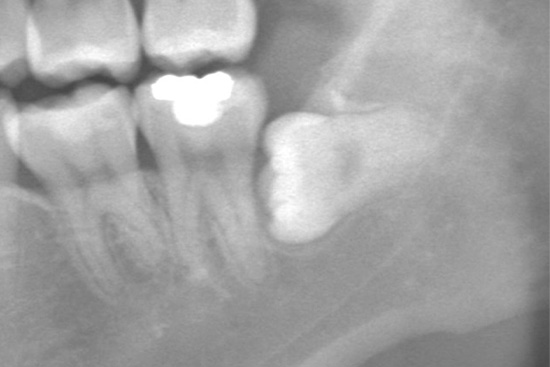

親知らず抜歯の症例

抜歯前

抜歯後

| 主訴 | 親しらずが気になる |

|---|---|

| 治療期間 | 1週間 |

| 治療内容 | 抜歯 |